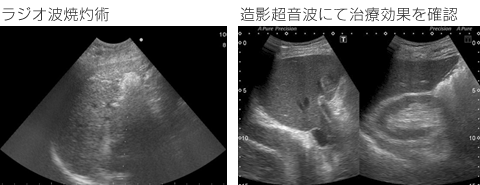

RFA(ラジオ波焼灼術)

肝臓癌に対して、その患部をラジオ波を用いて焼いて治療する方法です。